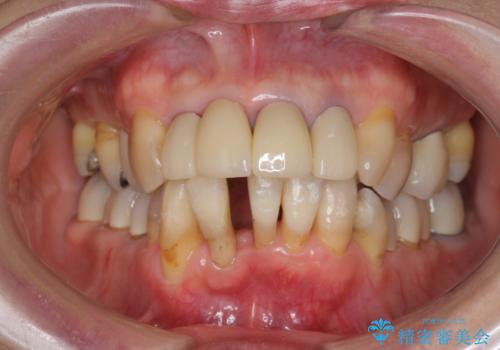

- 上顎前歯の黒ずみの改善、下顎前歯の十度なガタつき、矯正治療とセラミック治療を含む全体的な治療を希望され来院されました。

銀歯を高強度の仮歯に替えたのち、下顎前歯のみの部分矯正→全体的なマウスピース矯正治療(インビザライン)→最終的なセラミック治療と治療を進めます。

矯正治療と目立つ銀歯のやりかえを行ったことでかみあわせだけでなく、審美性・清掃性も改善し口腔内の環境を劇的に改善することができました。